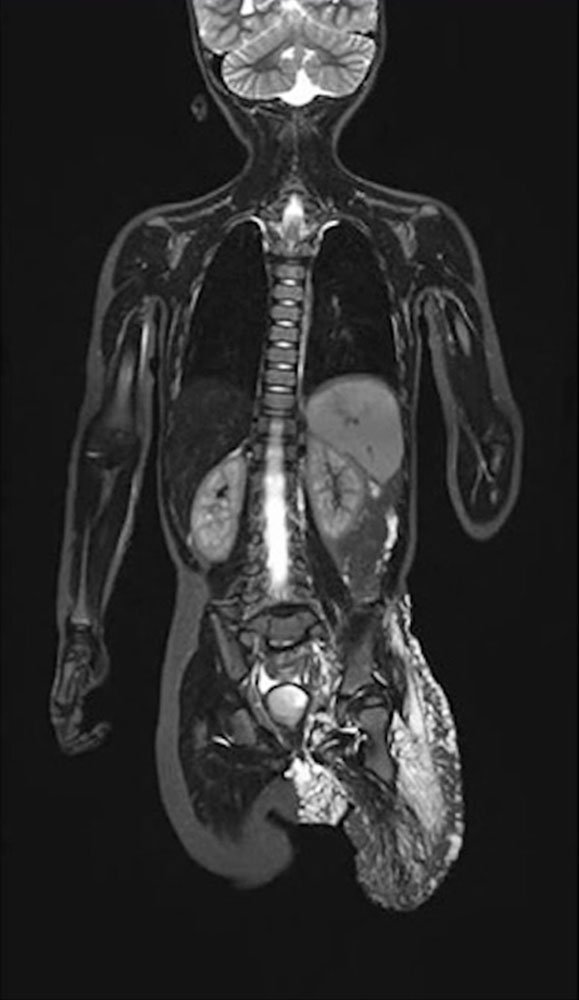

Bei Patienten mit Gefäßanomalien sollte in der Regel nach Diagnostik einer Skoliose ein MRT der Wirbelsäule folgen, um unterscheiden zu können, ob die Wirbelsäulenverkrümmung auf eine Gefäßmalformation im Bereich der Wirbelsäule selbst (z. B. beim CLOVES-Syndrom) oder eine mögliche Beinlängendifferenz zurückzuführen ist. Oder aber, ob es sich um eine idiopathische Skoliose handelt, die unabhängig von der Gefäßmalformation bei dem Patienten vorhanden ist.